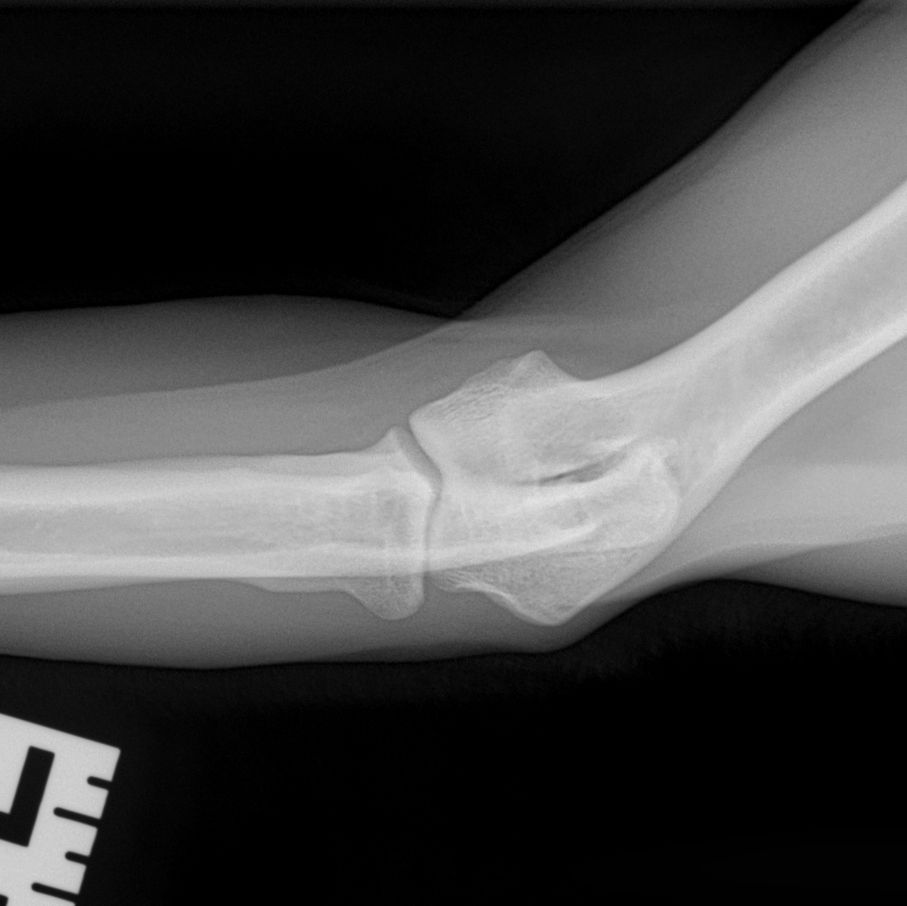

Hieronder foto's van Guus genomen met onze nieuwe DRgem rontgen. Beoordeeld met de hoogste score door de Raad van Beheer op Kynologisch gebied

Elleboogdysplasie (ED) onderzoek

Elleboogdysplasie is een ontwikkelingsstoornis van de ellebooggewrichten, met name het kraakbeen is aangetast. Deze aandoening kan erfelijk zijn, maar omgevingsfactoren spelen soms ook een rol. Er zijn honden die op jonge leeftijd al problemen ondervinden door ED, soms komt het pas op latere leeftijd tot uiting. Om te kunnen zien of uw hond ED heeft zijn röntgenfoto’s van de ellebogen nodig.

Voor een aantal rassen is een diagnose-onderzoek verplicht. Bij dit onderzoek dienen er per elleboog vier foto’s in vier verschillende richtingen gemaakt te worden (dus in totaal 8 foto’s). Deze rassen zijn: Labrador Retriever, Golden Retriever, Chesapeake Bay Retriever, Rottweiler, Berner Sennenhond, Duitse Herdershond, Bordeaux Dog.

Voor alle andere rassen volstaat een onderzoek met twee foto’s per elleboog. Meestal passen wij een lichte sedatie toe bij het maken van de officiële ED-foto’s. Dit is nodig om een kwalitatief goede foto te maken, welke aan de hoge eisen van de beoordelingscommissie moet voldoen. Uw hond moet op zijn of haar zijde en borst liggen, waarbij de elleboog in verschillende houdingen wordt gelegd.